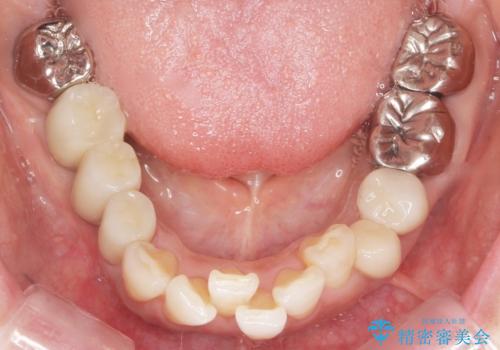

- 虫歯と歯並びを治したいとご希望された患者様です。

精査したところ、左下の小臼歯(左下5)の銀の詰め物の下に大きなう蝕を認めました。

またその手前の歯(左下4)は頬側転位していることを気にされておりました。